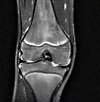

MRI of the knee joint.

МРТ коленного сустава. Метод неинвазивного диагностического обследования области коленного сустава с использованием электромагнитных волн и постоянного магнитного поля для получения послойного изображения высокой точности. Используется для выявления воспалительных и деструктивных процессов, отклонений в строении сустава, применяется в процессе диагностики поражений мениска и связочного аппарата, сложных переломов, вывихов и переломов поражений. Исследование показано для визуализации опухолей и во время предоперационной подготовки пациентов. Магнитно-резонансная томография коленного сустава является высокоинформативной безопасной процедурой, обычно выполняемой на амбулаторном уровне, она может быть нативной или контрастной.

Магнитно-резонансная томография колена использовалась в диагностических целях в течение нескольких десятилетий и является наиболее точным методом визуализации, особенно для образований мягких тканей, расположенных внутри и вокруг сустава. Изображения высокого разрешения, связанные с реакцией клеток на электромагнитное излучение. Полученный сотовый отклик фиксируется датчиками с созданием серии черно-белых изображений. МРТ коленного сустава является распространенным методом обследования в области травматологии, ортопедии и спортивной медицины, применяется при диагностике ревматологических и онкологических заболеваний.